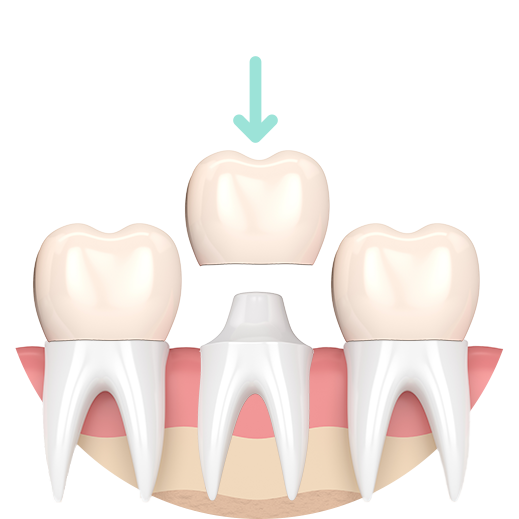

Preparation for a Crown

Damaged natural crown

Reshaped tooth

Porcelain crown

How is a crown done?

Your dentist will perform a thorough examination to determine if a crown is needed. The tooth is trimmed to make space, and impressions are taken to create a custom crown in a dental laboratory. Once ready, the crown is firmly cemented over the tooth.